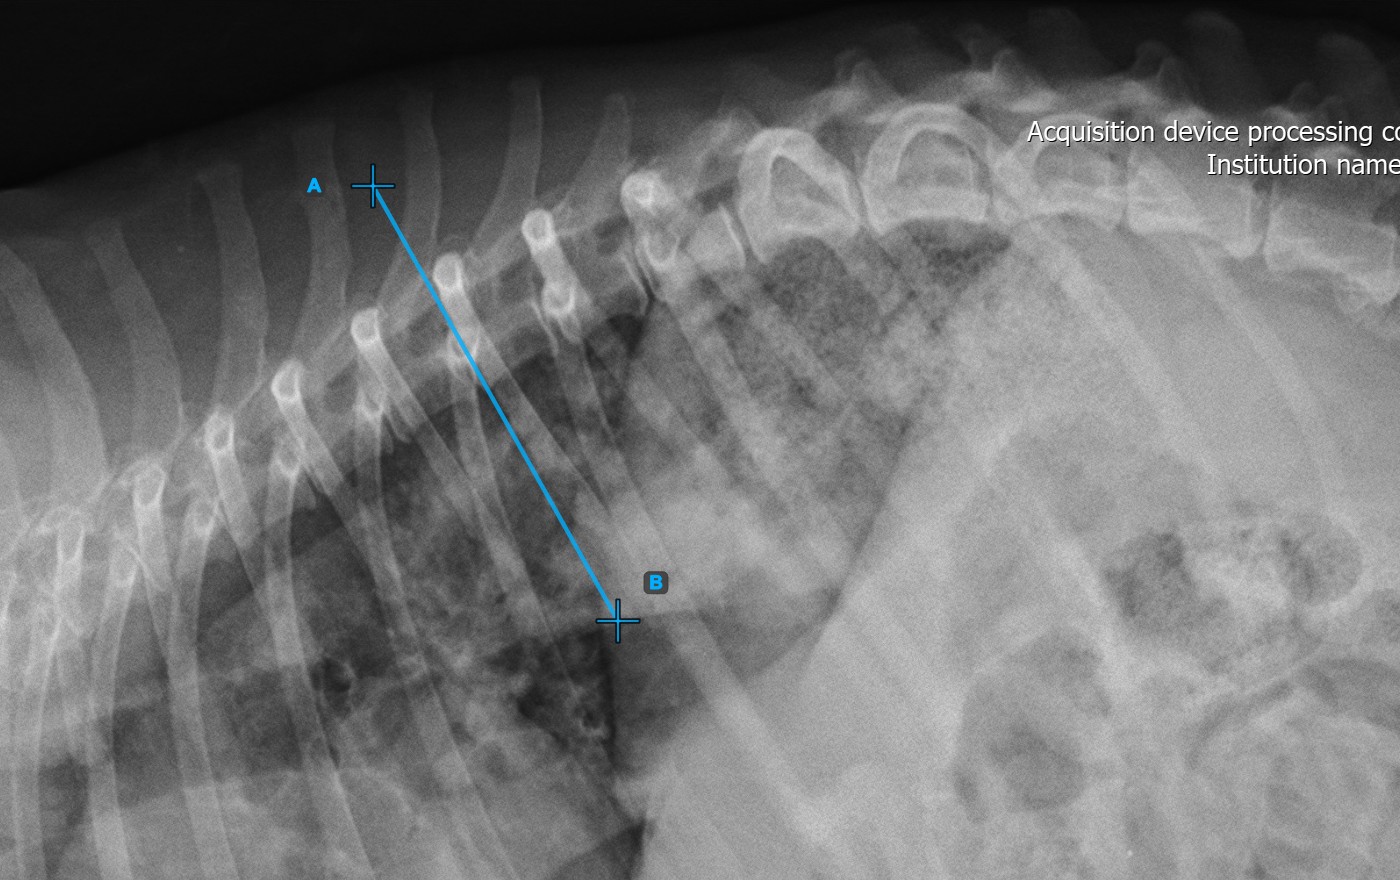

Das Bild unten zeigt eine typische Platzierung der ersten Wirbellinie.

../../_images/image373.jpg